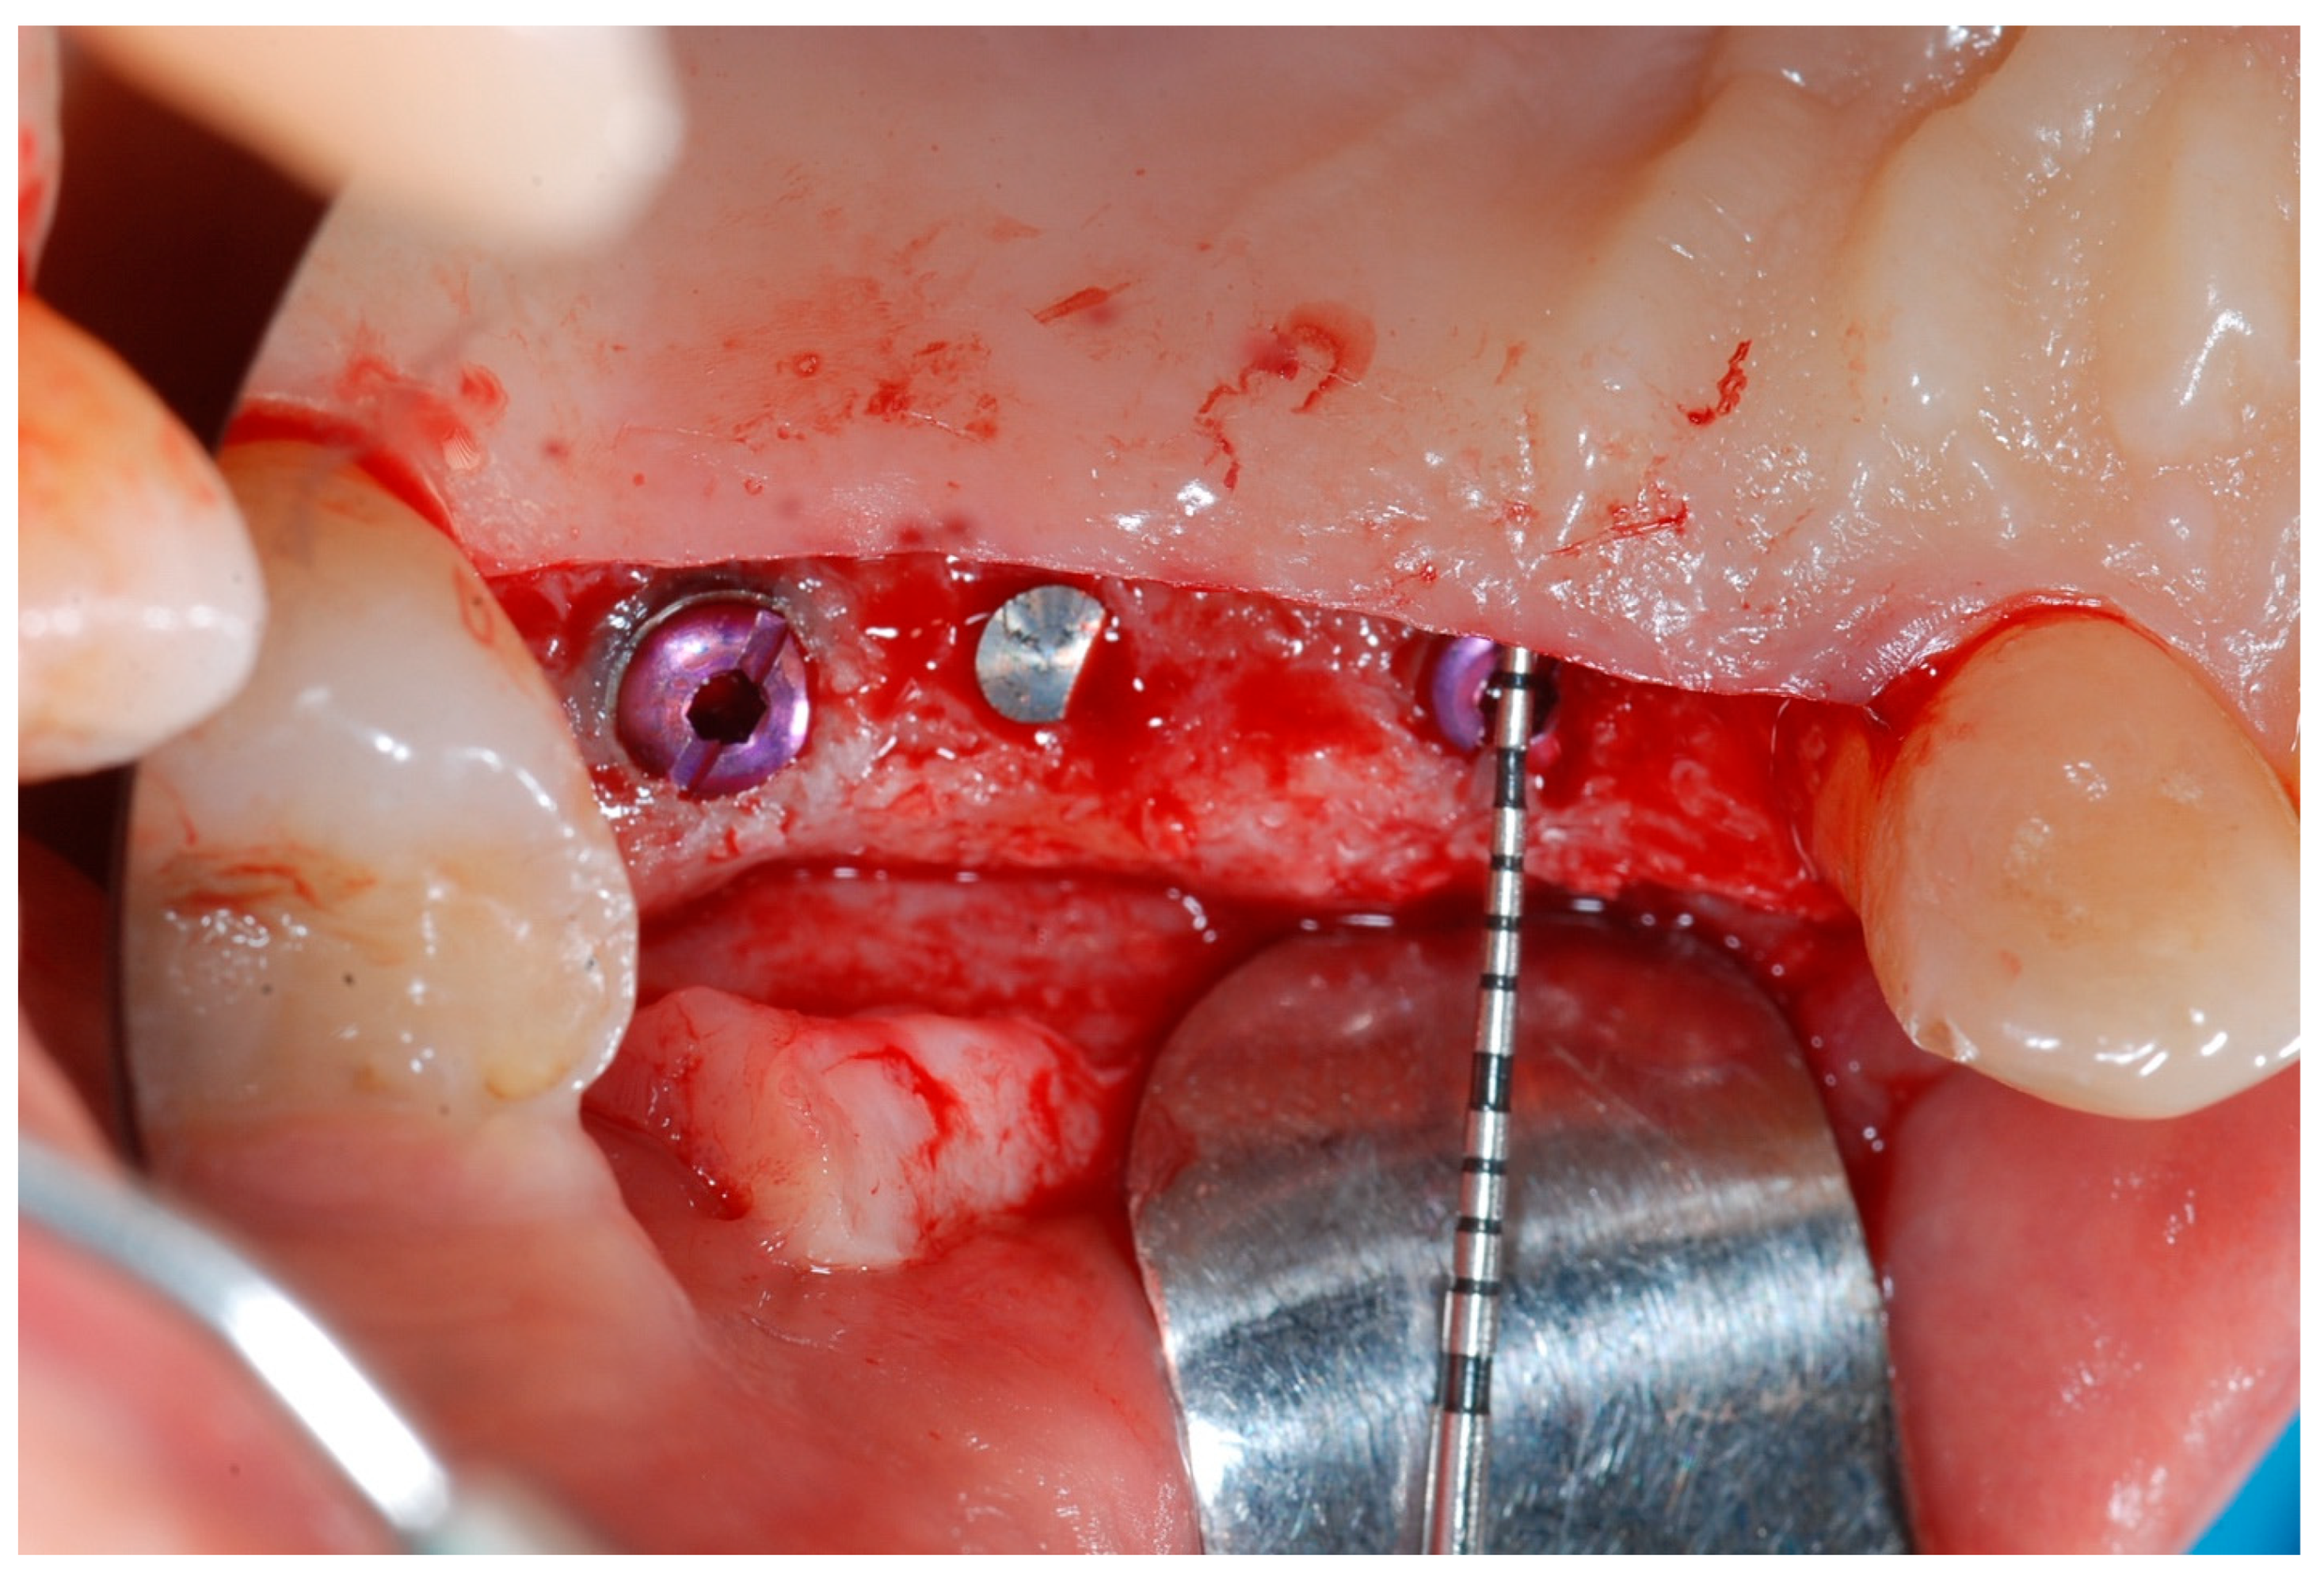

Six months following augmentation, re-entry surgery was carried out to uncover the implants and connect the healing abutments. Following chlorhexidine rinses and the injection of local anesthetics, crestal incisions as well as releasing incisions along the same lines as the ones during augmentation surgery were performed. Mucoperiosteal flaps were raised in order to visualize the augmented bone volume (Figure 9 and Figure 10).

Figure 9.

Reopening surgery showing no membrane residues and obtained buccal bone thickness.

Figure 10.